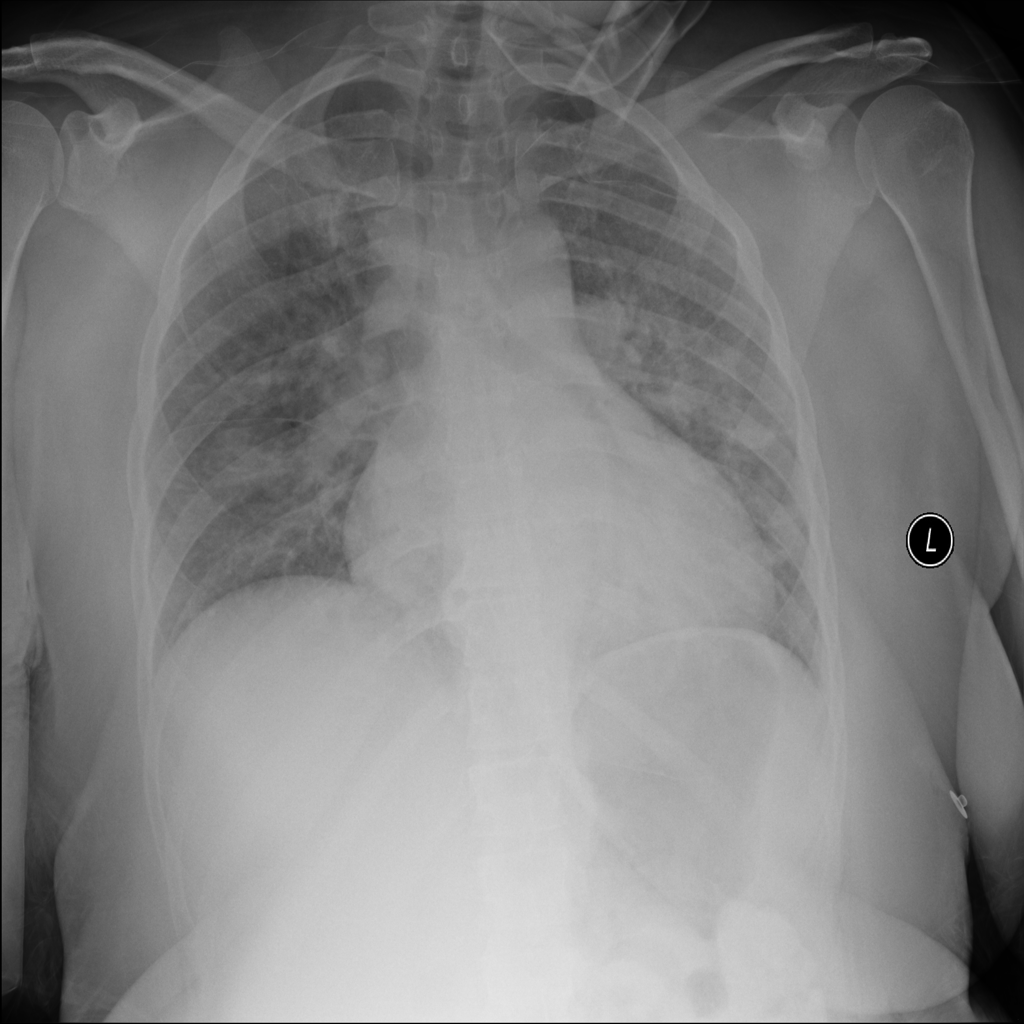

Nodule

A nodule is a small rounded opacity in the lung or chest field. It is a descriptive imaging finding that can be benign or more concerning depending on size, appearance, and context.

Showing up to 90 reference images for Nodule.

PAT-50E5 · IMG-000Nodule

PAT-50E5 · IMG-000

PA